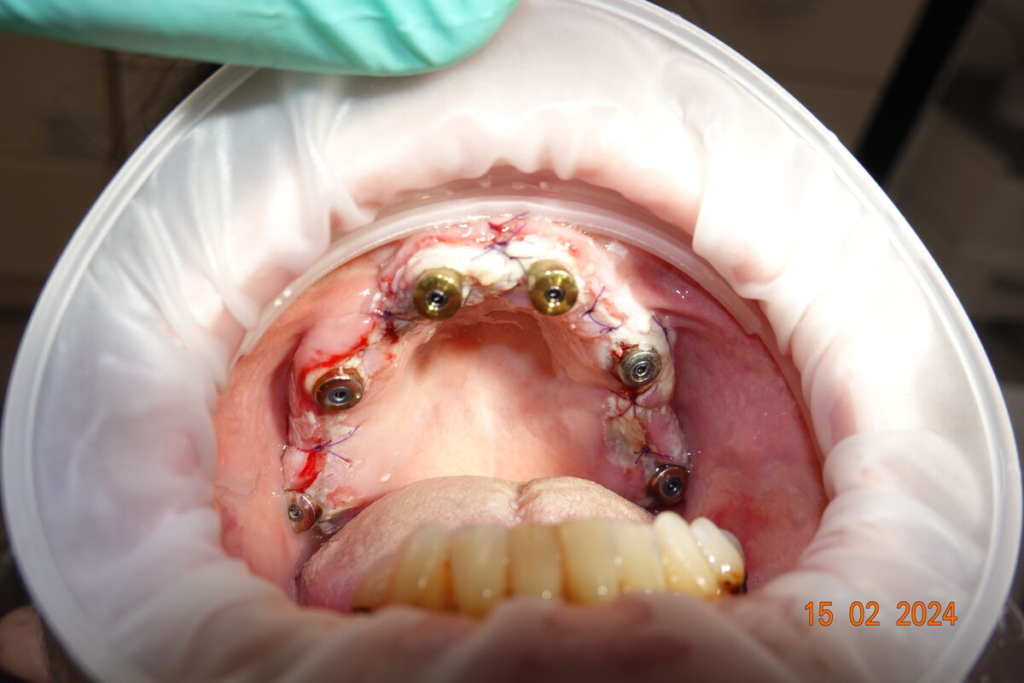

2. Chirurgický den

- případné vytažení zubů a implantace v jeden den

- 4–6 implantátů metodou All-on-X

- digitální otisky pro rychlou výrobu zubů

Technika All-on-X — I. fáze